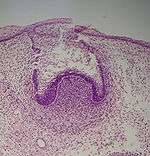

Cap stage

Histologic slide of tooth in cap stage.

The first signs of an arrangement of cells in the tooth bud occur in the cap stage. A small group of ectomesenchymal cells stops producing extracellular substances, which results in an aggregation of these cells called the dental papilla. At this point, the tooth bud grows around the ectomesenchymal aggregation, taking on the appearance of a cap, and becomes the enamel (or dental) organ covering the dental papilla. A condensation of ectomesenchymal cells called the dental sac or follicle surrounds the enamel organ and limits the dental papilla. Eventually, the enamel organ will produce enamel, the dental papilla will produce dentin and pulp, and the dental sac will produce all the supporting structures of a tooth, the periodontium.[1]